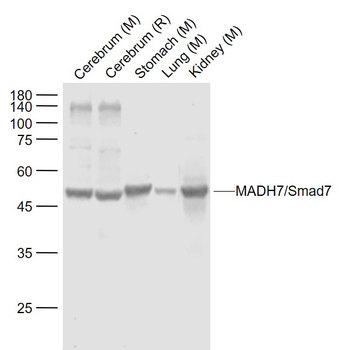

100 μl, 200 μl, 50 μlSMAD7 Rabbit Polyclonal Antibody [orb500819]

FC, ICC, IF, IHC-Fr, IHC-P, WB

Bovine, Porcine

Human, Mouse, Rat

Rabbit

Polyclonal

Unconjugated

100 μl, 200 μl, 50 μlPhospho-Smad3 (Ser213) Rabbit Polyclonal Antibody [orb106193]